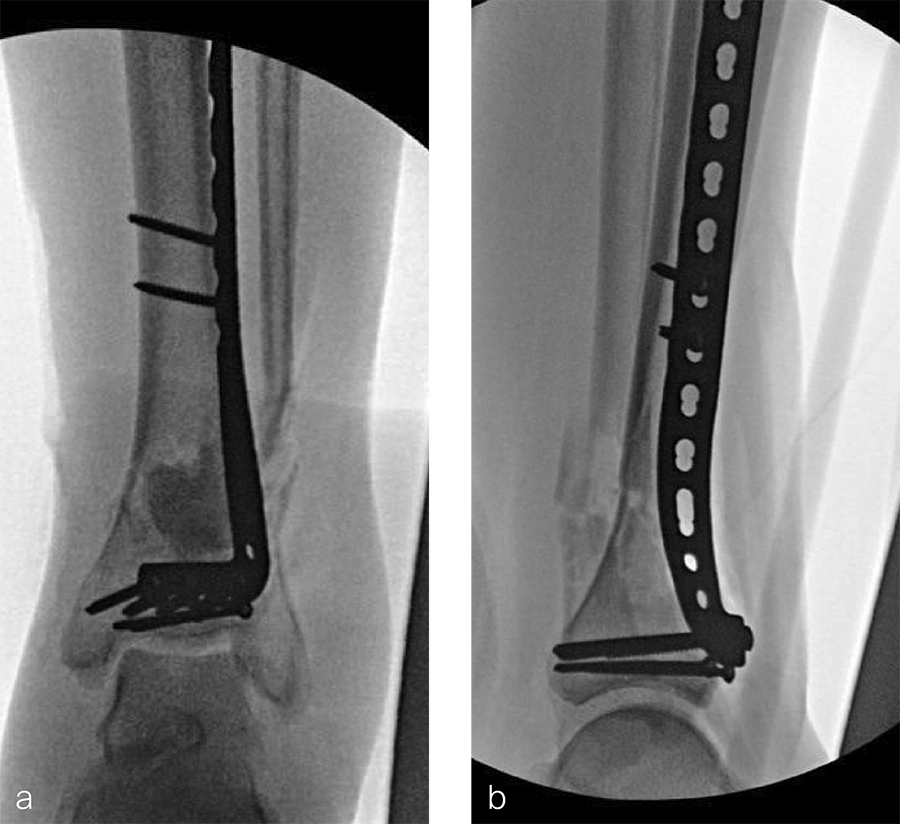

Two months later, the patient had a staged cement spacer removal and hardware removal followed by a new spacer placement (Fig 4). When microbiological cultures were negative for 5 days he was taken to the OR for definitive fixation and bone grafting. RIA bone graft from the ipsilateral femur was taken, a new anterior lateral plate was placed with an adjunct IM nail (and angle stable screws) as the distal plafond was now one articular block (Fig 5).